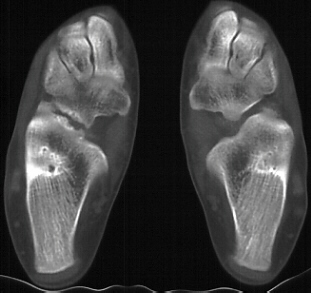

Radiographs - AP, lateral, oblique at 45 degrees, and Harris view. A coalition may be difficult to pick up on the AP and lateral views due to the overlap of bones but there may be some subtle clues. Beaking of the talus or narrowing of the subtalar joint may be present. Calcaneonavicular bony bridges can be seen on the lateral view with the classic "anteater nose" coming from the calcaneous. Harris view may be helpful to evaluate the subtalar joint but a CT is often obtained to rule out subtalar coalition. The ankle may remodel to a ball and socket joint secondary to limited subtalar motion. Coronal CT cuts are most helpful in evaluating talocalcaneal bony bridges while transverse cuts are used for calcaneonavicular bars.